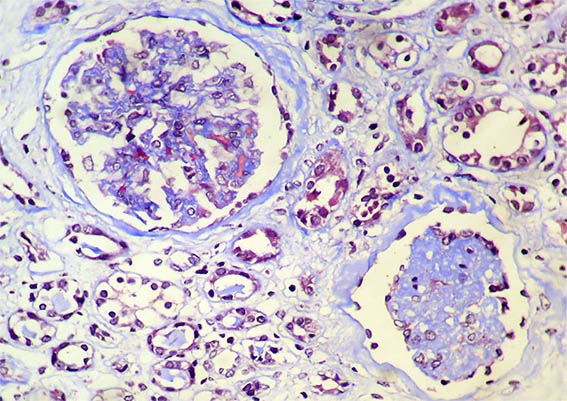

Se hace biopsia renal con impresión diagnóstica de lesión renal aguda. Ver las imágenes.

Figura 1. Trcrómico de Masson, X100.

Figura 2. Tricrómico de Masson, X200.